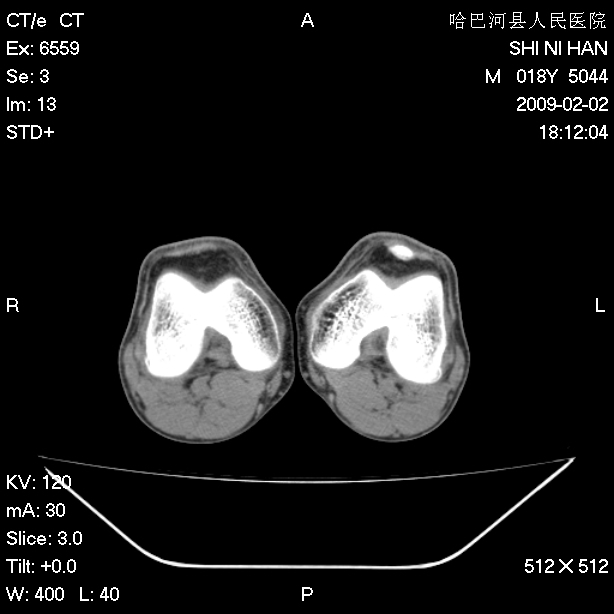

标题: CT17889:外伤后右膝关节反复疼痛3年余 [打印本页]

标题: CT17889:外伤后右膝关节反复疼痛3年余

ct未见明显异常。关节腔未见明显积液,半月板未见明显撕裂。但最好还是mri看看韧带及半月板情况。